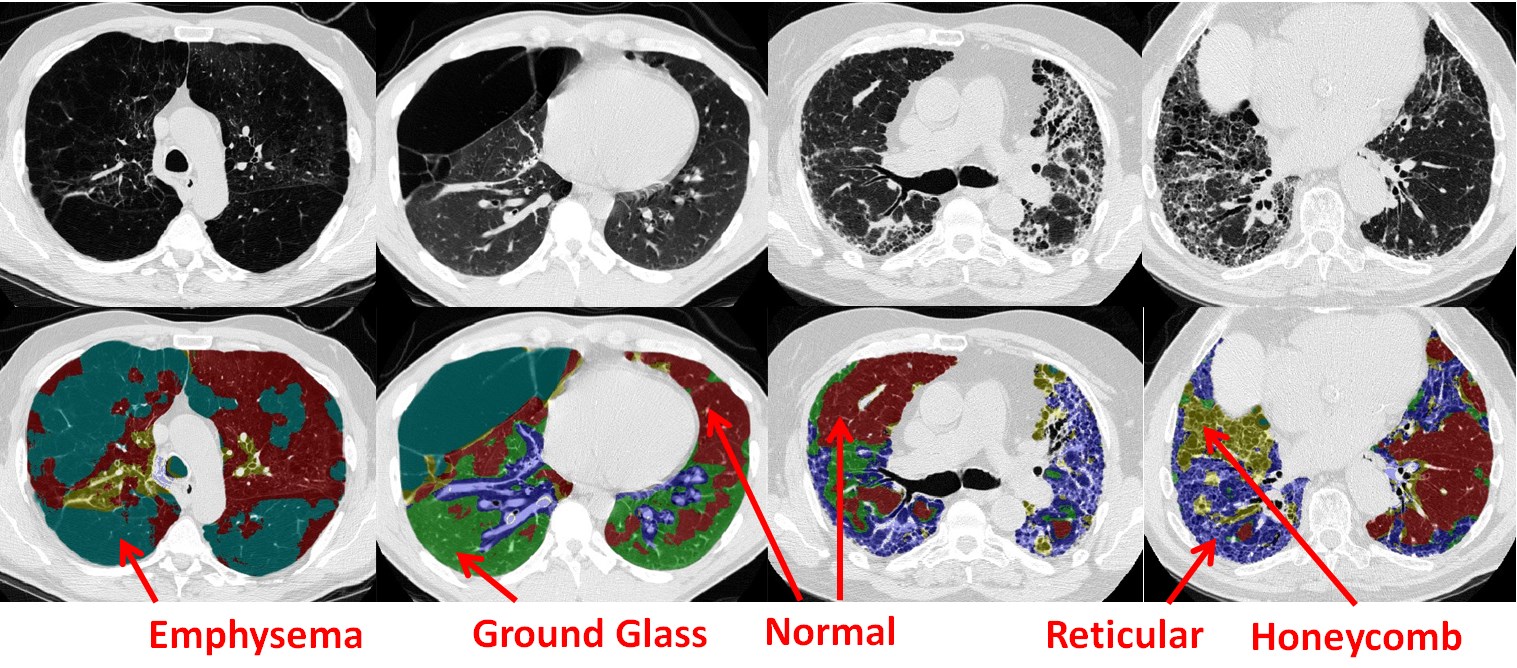

Interstitial lung disease (ILD) refers to a group of more than 150 chronic lung diseases characterized by progressive scarring or inflammation of lung tissues and eventual impairment of breathing. The gold standard imaging modality for ILD diagnosis is computed tomography (CT) [1, 2]. Figure 1 depicts several examples of some most typical ILD-related CT imaging visual patterns. Automated detection of ILD patterns from CT images would aid the diagnosis and treatment of this morbidity.